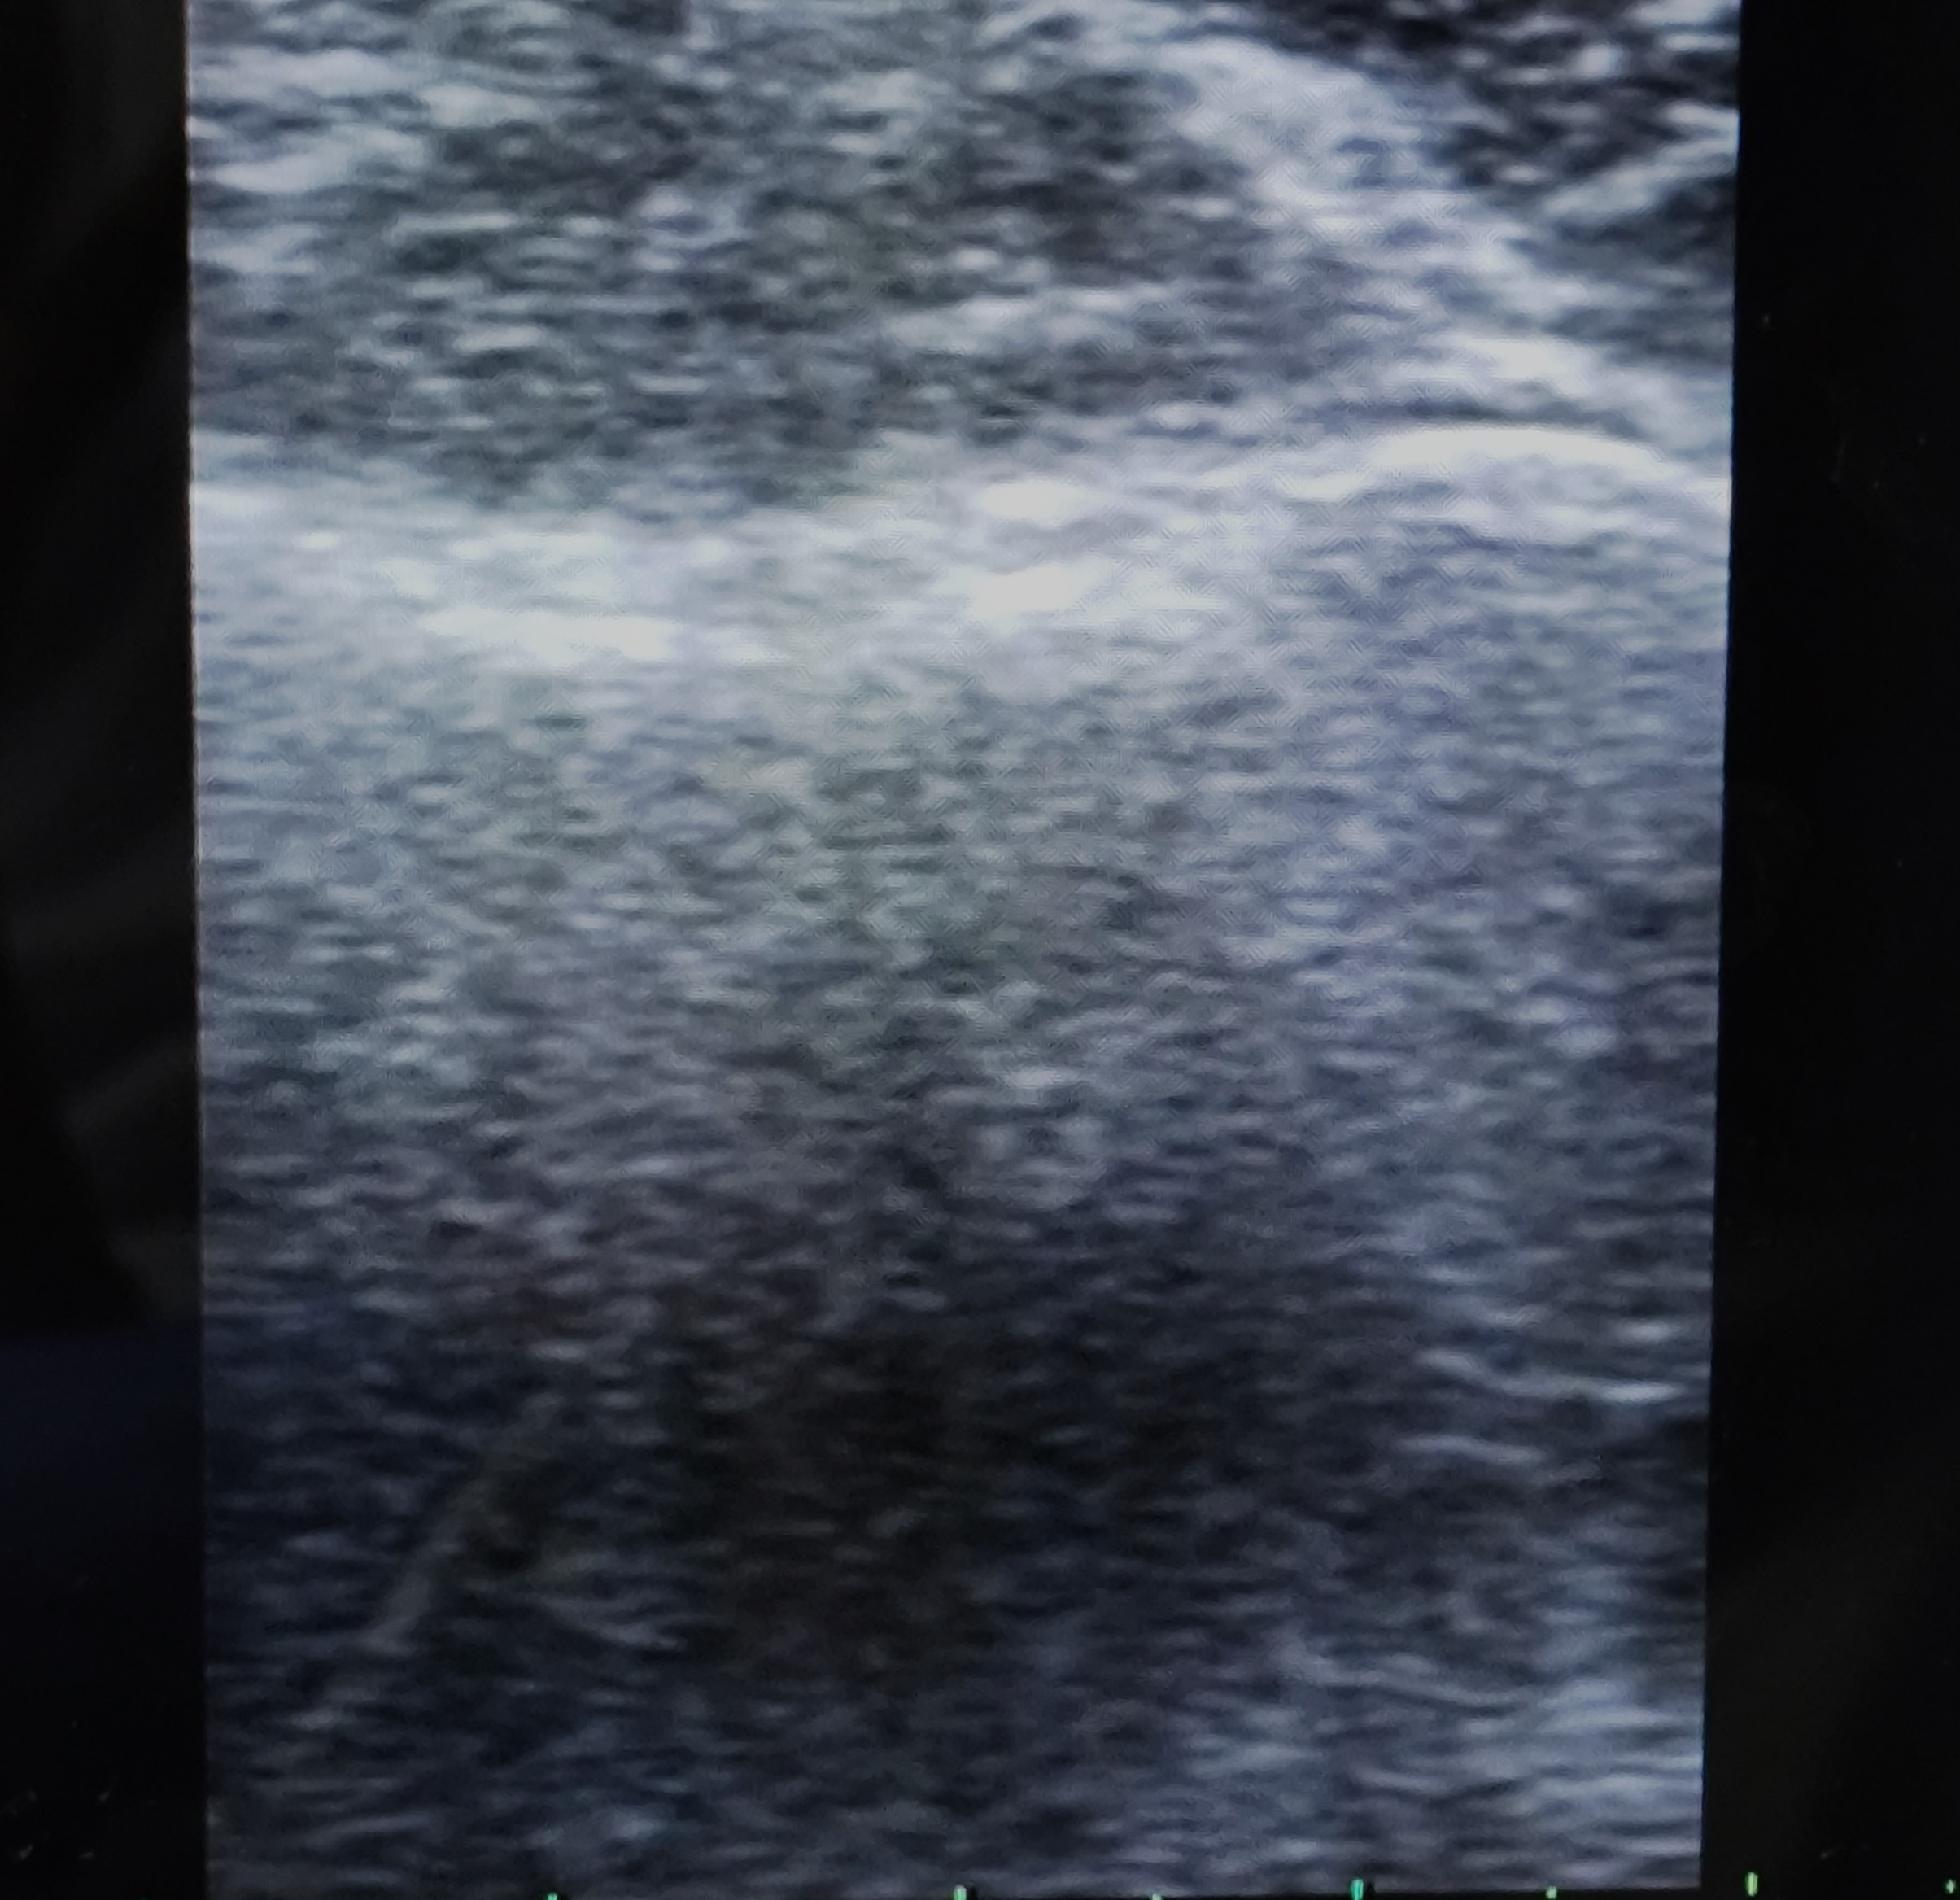

Hombre de 68 años que consulta por lesión quística/nodular en codo izquierdo de varios años de evolución con incremento de molestias al roce y apoyo en las últimas semanas. Sin otra sintomatología por aparatos ni otras articulaciones afectas.

Descripción de los hallazgos ecográficos y las imágenes más relevantes para la resolución del caso

La gota es una enfermedad metabólica crónica que causa depósitos de cristales de urato en tejidos blandos y articulaciones; este caso clínico ilustra un ejemplo, donde un tofo nodular en el codo se convierte en el motivo principal de consulta. La ecografía clínica permitió detectar las características típicas de dicha enfermedad, facilitando un diagnóstico presuntivo sólido y guiando de forma adecuada las decisiones terapéuticas.